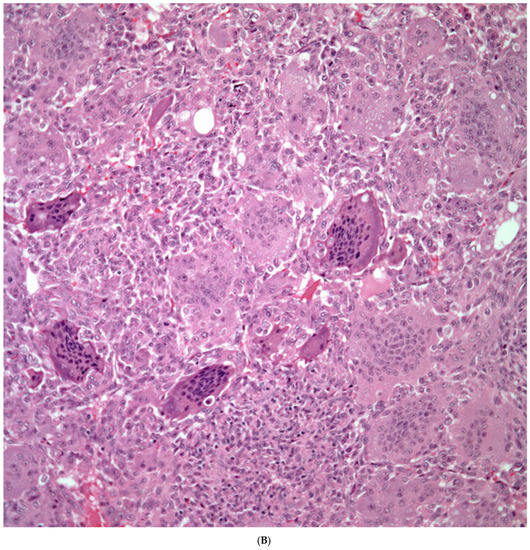

Giant Cell Carcinomas: These tumors may show predominantly a neoplastic cellular proliferation composed exclusively of multinucleated giant cells or a predominantly giant cell carcinoma (Figure 5A,B) or associated with a conventional non-small cell carcinoma like adenocarcinoma or squamous cell carcinoma. The giant cell carcinoma may show giant cells of the syncytiotrophoblastic, osteoclastic, or null cell type. The giant cell carcinomas of the null cell type characteristically show a prominent inflammatory background and giant cells engulfing inflammatory cells (emperipolesis) (Figure 6A,B). The tumors composed of osteoclast-like giant cells show giant cells like those described in bone tumors (Figure 7A,B).

Figure 7.

(A) Carcinoma associated with osteoclast giant cells; (B) Osteoclast giant cells like those in bone tumors.